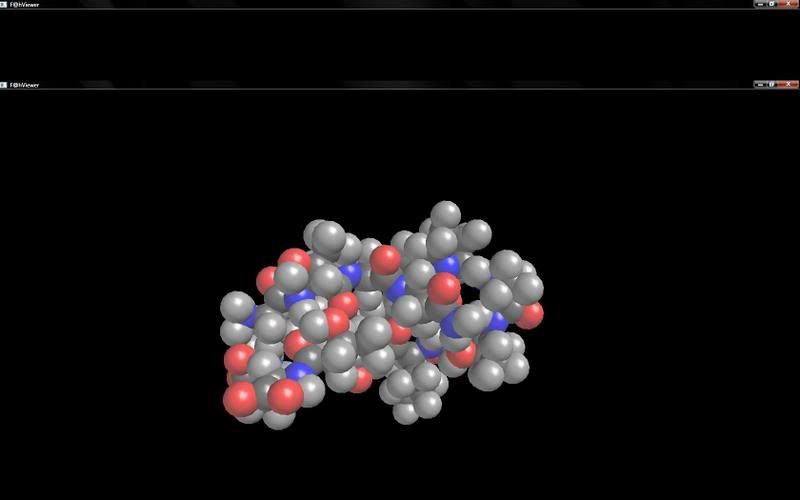

ÉG er bara að hvetja alla til að kíkja á Folding@home sem eiga alvöru tölvur , sérstaklega þá sem eru með hd 4750+ eða betra því þau kort geta afkastað hrikalega í folding@home miðað við nvidia kort

þetta gæti verið lækningin við alzheimerinum sem þú eða þínir gætu fengið í framtíðinni í fúlustu alvöru

Ati radeon 4870 með sína 800 stream processora tekur svona vinnslu í nefið miðað við öflugustu Nvidia kort sem fara bara í vesen við að reyna við þetta

þetta gæti verið lækningin við alzheimerinum sem þú eða þínir gætu fengið í framtíðinni í fúlustu alvöru

ég veit að ég er hérna heima hangandi í vinnslys fríi og hef ekkert betra að gera en að benchmarka , en þetta hljómar ekki heimskulegt damn lamer að greinast með alzheimer, krabbamein..seinna á lífsleiðini en þarna er manni gefið tækifæri til að hjálpa öðrum og husanlega sjálfum sér seinna meir